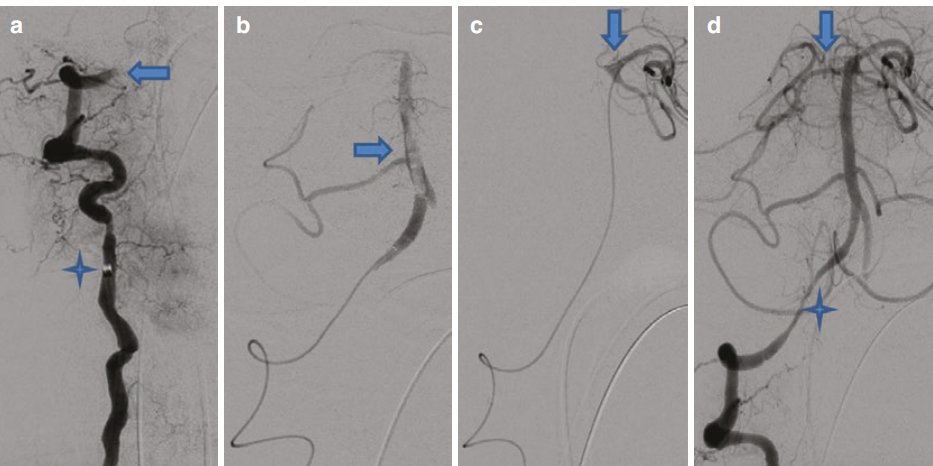

一位61岁男性,出现共济失调及行走困难症状1周。随后,其症状急剧加重,表现为右侧肢体无力、向左凝视偏斜以及嗜睡。该患者需行气管插管。进一步的神经影像学检查显示,双侧椎动脉颅内段闭塞并伴有基底动脉血栓形成,经诊断性脑血管造影得以确诊。将Neuron MAX导管置入左侧锁骨下动脉,借助Velocity微导管及Synchro 14微导丝,将JET D抽吸导管推进至左侧椎动脉颈部远端 。由于C1-C2 水平存在闭塞情况,微导管无法向颅内进一步推进。因此,将 Neuron MAX 导管选择性地推送至右侧锁骨下动脉,随后将再灌注系统推进至右侧椎动脉颈部远端。在路图成像技术引导下,借助微导丝成功将 Velocity 微导管穿过闭塞部位。超选择性血管造影检查明确了基底动脉血栓形成,之后将微导管进一步推送至左侧大脑后动脉(PCA)近端。随后,使用6 毫米×40 毫米的 Solitaire 取栓支架并持续运用 JET D 抽吸装置,将其推进至 V3节段进行机械取栓操作 。最终数字减影血管造影(DSA)检查结果显示,基底动脉实现完全再通,不过右侧椎动脉V4节段仍残留严重狭窄。由于右侧大脑后动脉持续闭塞,最终实现了脑梗死溶栓分级(TICI)2b 级的再灌注(见图 2) 。

图2基底动脉取栓术相关影像呈现 :(a)图中显示,JET 7 抽吸导管(标注为星号)置入右侧椎动脉颈部,同时可观察到V4节段存在完全闭塞情况(以箭头指示)。(b)经超选择性微导管注入造影剂后,清晰显示出基底动脉内的血栓(箭头所指处)。(c)再次进行超选择性微导管造影,结果表明微导管尖端(箭头所示)已到达左侧大脑后动脉近端血栓负荷的远心端位置。(d)最终数字减影血管造影(DSA)检查结果显示,基底动脉实现再通,但V4 节段仍持续存在严重狭窄(标注为星号),且右侧大脑后动脉依旧处于闭塞状态(箭头指示 )。